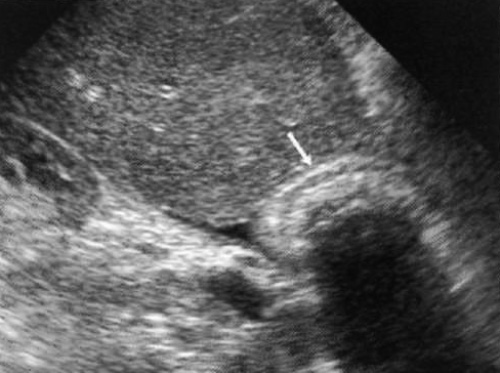

Фригийский колпак (деформация в виде фригийского колпака) возникает в результате складывания дна желчного пузыря в направлении тела, что является вариантом нормы (обнаруживается примерно у 4% пациентов). Ультразвуковая картина демонстрирует толстую складку, которая напоминает перегородку (фото 2).

Фото 2. «Фригийский колпак». УЗИ в продольной проекции демонстрирует деформацию желчного пузыря в виде фригийского колпака (указан стрелками) – вариант нормы